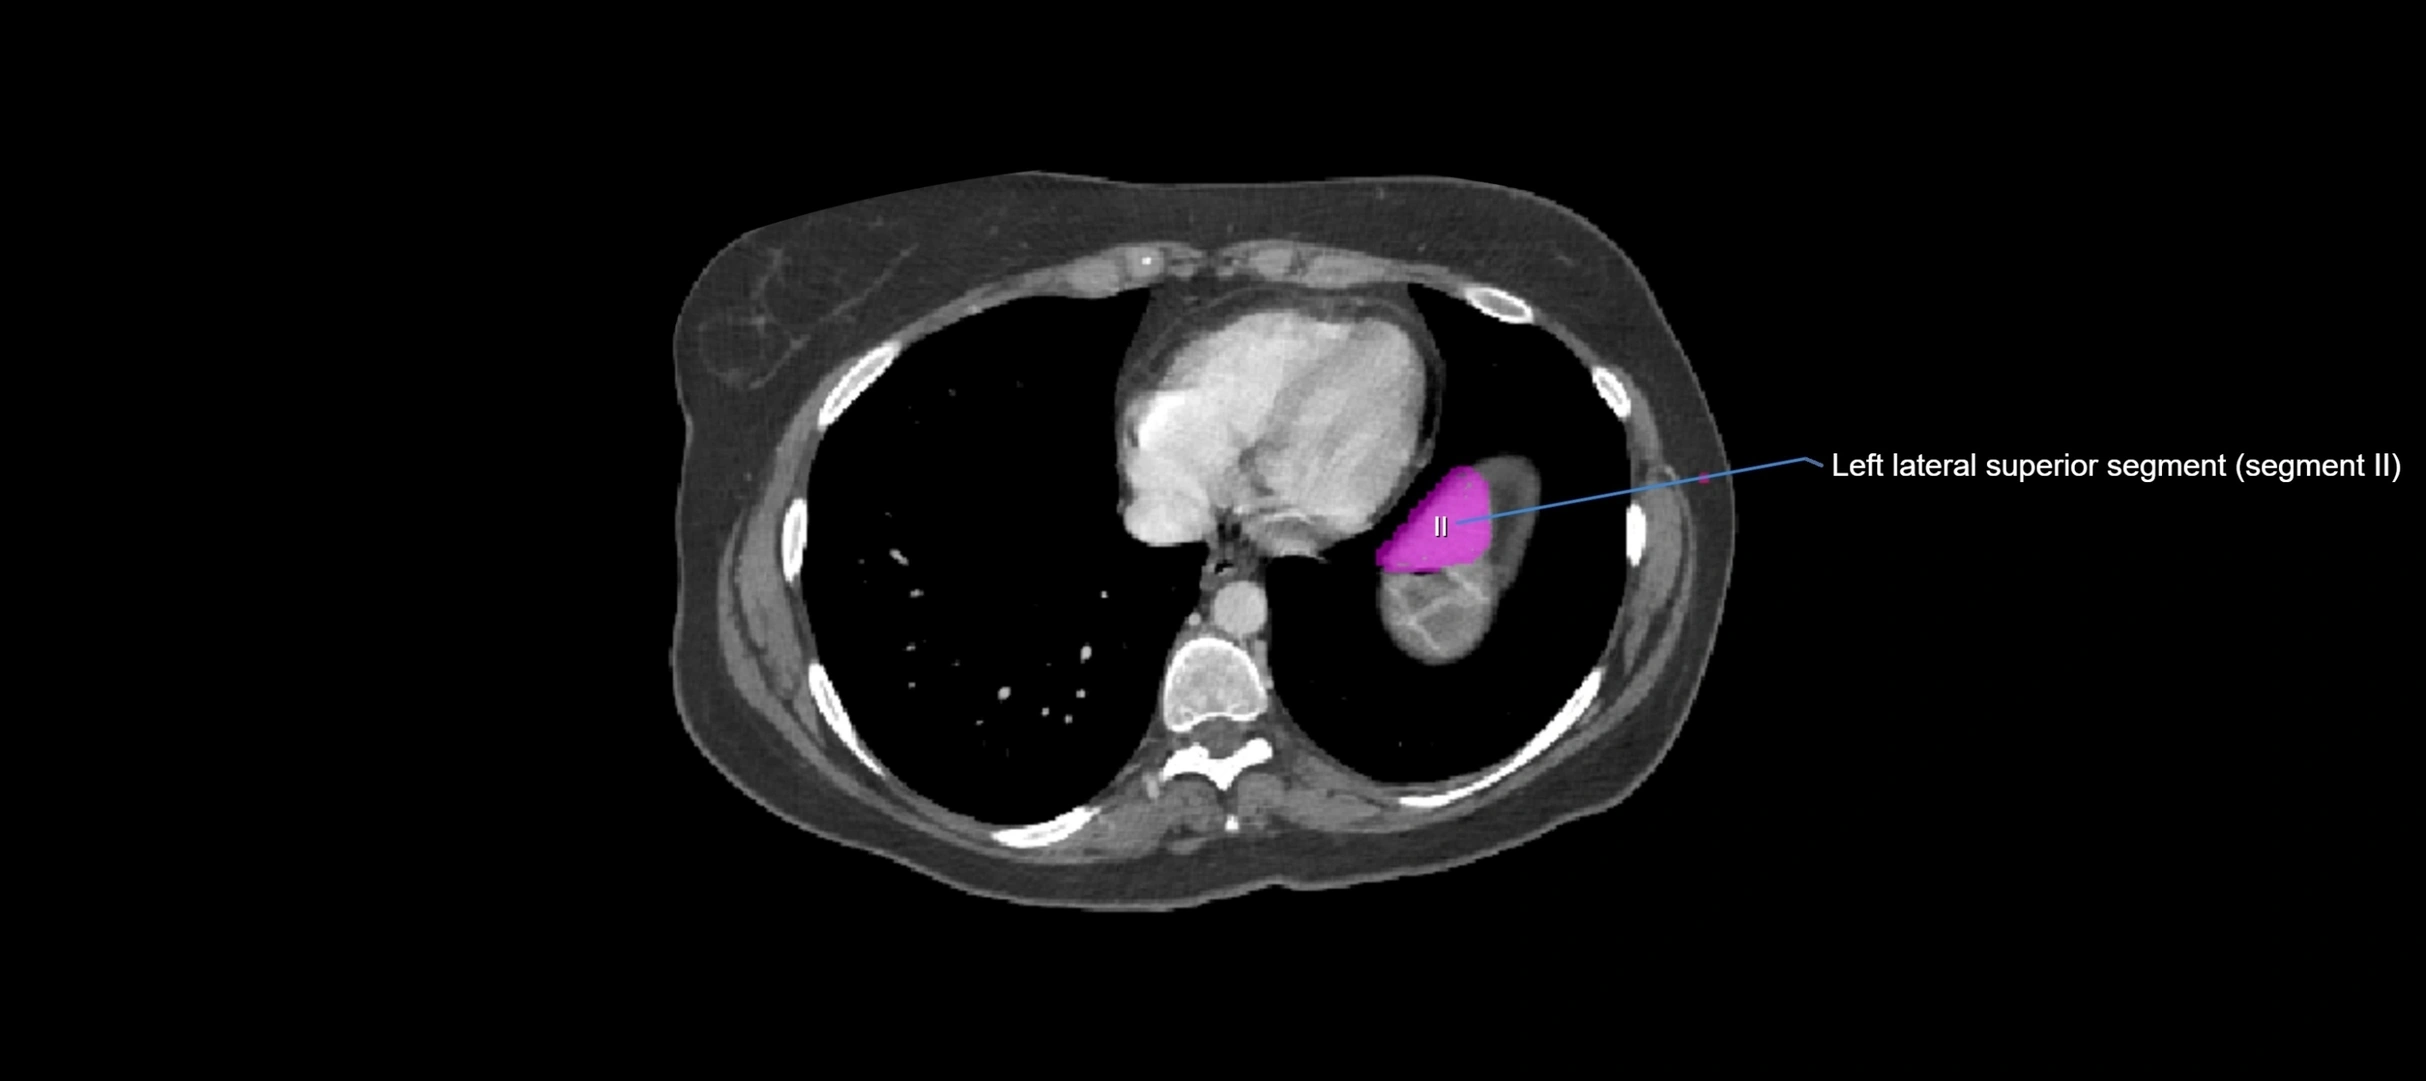

MRI image

image

MRI Appearance

T1-weighted images:

• Parenchyma shows intermediate signal intensity, similar to rest of liver

• Lesions (tumors, fat, fibrosis) show altered signal compared to background liver

T2-weighted images:

• Normal parenchyma shows intermediate to slightly hyperintense signal

• Pathologies (cysts, hemangiomas, tumors) demonstrate variable high signal